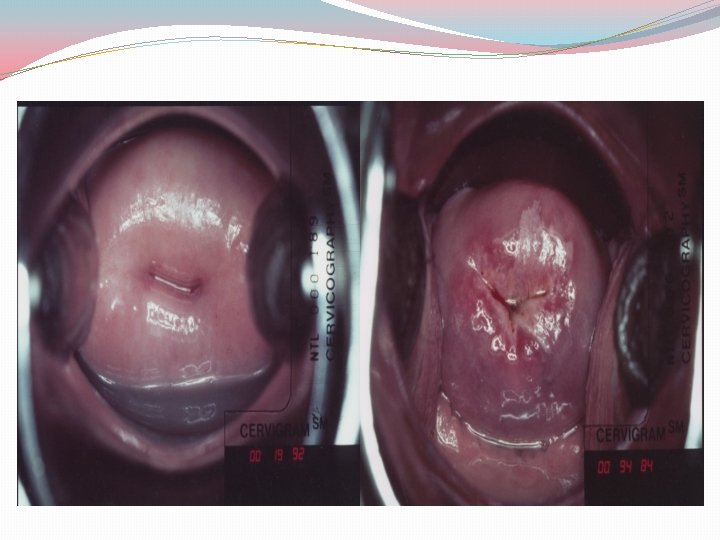

OTHER SCREENING MODALITIES �Visual inspection (Unmagnified visualization of cervix) Visual inspection with acetic acid (VIA) or Lugol's iodine is used for cervical cancer screening in some developing countries �Aceto white changes after application may indicate : Abnormal transformation zone Areas of increased cellular density with increased abnormal nuclei and DNA content

VIA Advantages �Quick, easy, and non-invasive �Requires minimal equipment �Results are immediately available �Good sensitivity-especially for higher grade lesions �Few false negatives

VIA Disadvantages �Lower specificity (more false positives) �Increased costs for referrals to colposcopy �Potential of unnecessary biopsies �Follow up of abnormal that don’t get colposcopies